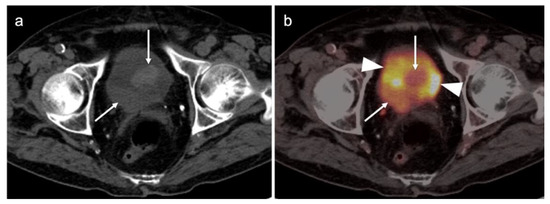

2.6. Vulvar Carcinoma